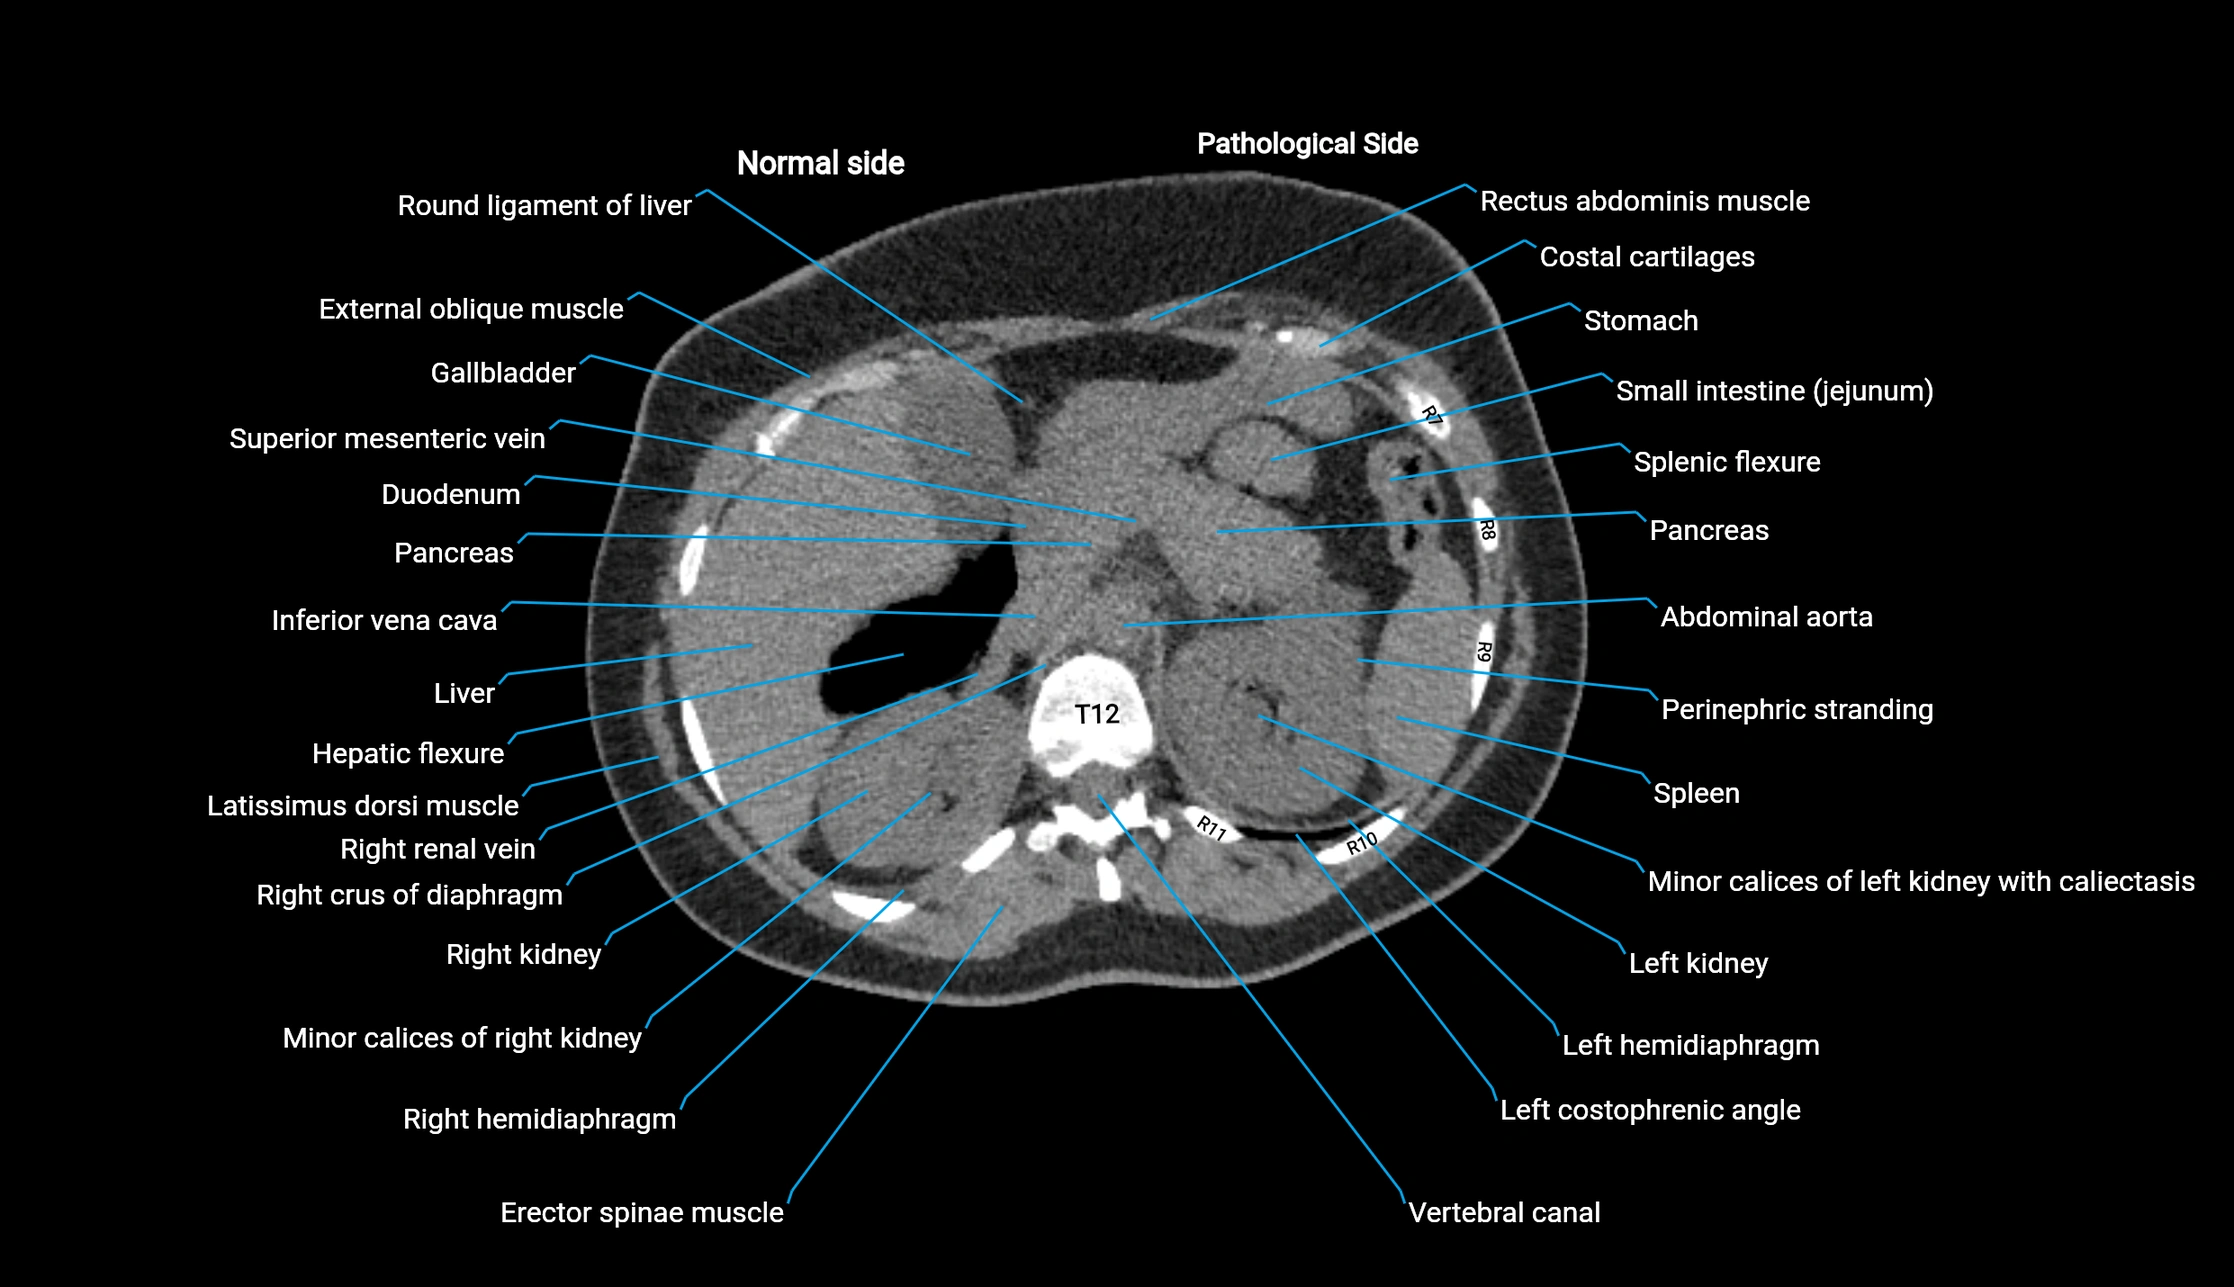

Post-Contrast CT (Contrast-Enhanced CT):

• Portal venous phase:

• Anterior right portal branch enhances intensely and homogeneously

• Clearly separates from posterior branch

• Branching pattern to segments V and VIII sharply defined

• Arterial phase:

• Slight enhancement but less conspicuous than in portal phase

• Coronal and sagittal reconstructions:

• Optimal visualization of segmental bifurcation

• Used for preoperative liver mapping

• CT liver segmentation:

• RAPV acts as the principal boundary landmark for dividing anterior vs. posterior right hepatic segments